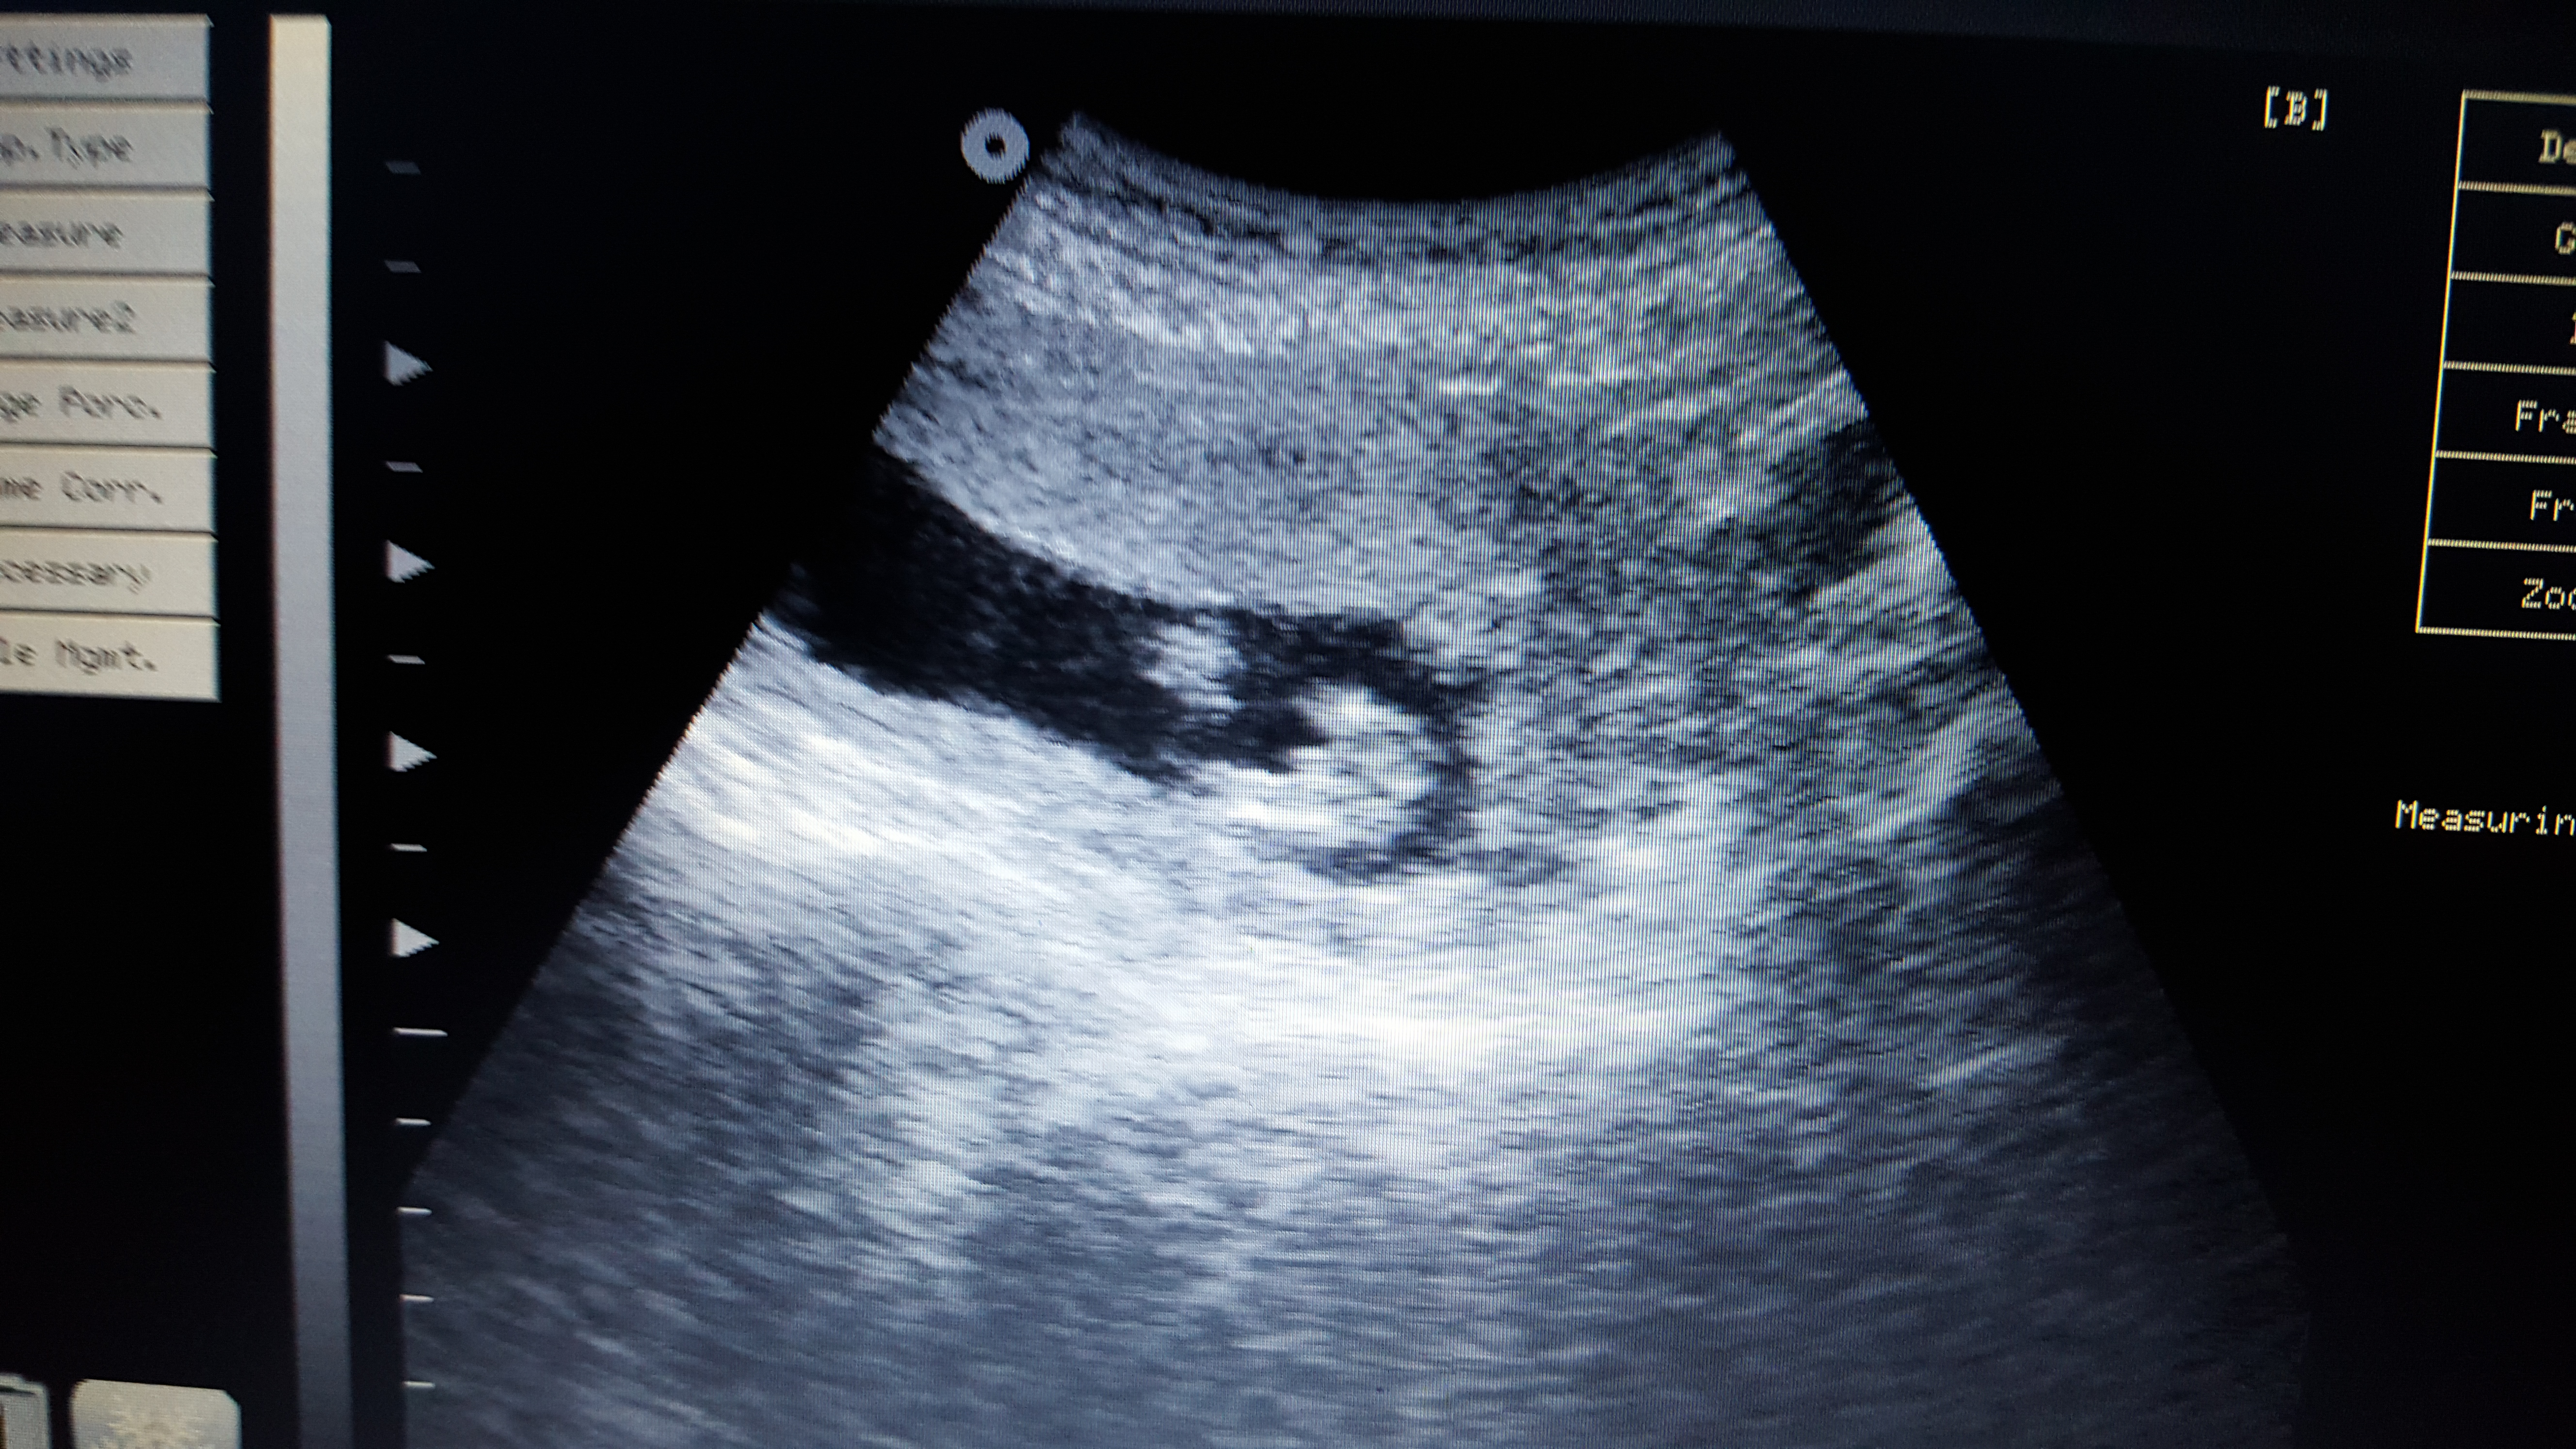

Pink or blue? These are taken at 13+3

Attachment 29185

Babies hands were around genital area alot so may of caught that in some of the photos!